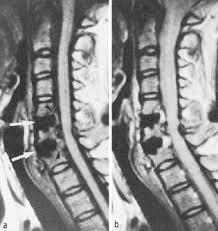

Auf dem MRT erkennt man ein deutliches Narbengewebe. Narbengewebe nach Bandscheiben-OP Zunächst sollte geklärt werden ob die Beschwerden tatsächlich vom Narbengewebe kommen. Habe vor einem Jahr Bandscheiben OP bei L45 mit anschließend 6 Wochen nicht sitzen und darauf 5 Wochen Reha gehabtDie eigentl.

Es kann vorkommen dass nach einer Wirbelsäulen OP Narbengewebe die Nerven bedrängt und das zu erneuten Schmerzen führt. Diese treten typischerweise einige Zeit nach der Operation auf Narben brauchen Zeit sich zu bilden.

Aber dann habe ich Schmerzen wie bei einem BS Vorfall mit starken Schmerzen und ziehen bis in die Wade. Drei Stunden nicht mehr liegen u muß. Diese treten typischerweise einige Zeit nach der Operation auf Narben brauchen Zeit sich zu bilden. Vor 6 Monaten wurde ich an der Bandscheibe L5S1 operiert. Die letzte op ist nun 4 Monate her. Die ideale Narbenpflege nach der OP Aus diesem Grund sollten Sie mit der Narbenbehandlung möglichst bald nach der OP beginnen. Hallo Nach drei BS OPs habe ich nun das Gefühl dass der Nerv durch Narbengewebe bedrängt wird. Hallo wer kann mir etwas zur Bildung von Narbengewebe nach Bandscheiben Operation sagen. Seltener sind Beschwerden nach einer Operation auf die Bildung von Narbengewebe zurückzuführen.